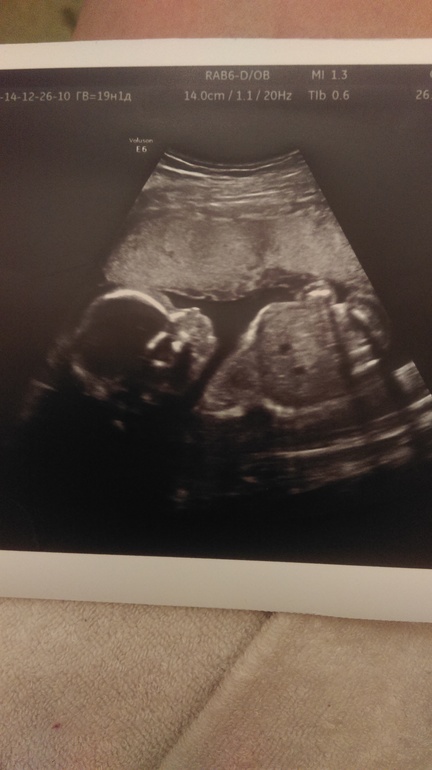

Результаты: УЗИ, КТГ, доплера, скринингаВсе у нас с малышом хорошо.развивается в срок 19нед,14см в длину и вес 321гр. Подтвердили мальчика.теперь самое время начинать думать над именем)) фото малышуна под катом